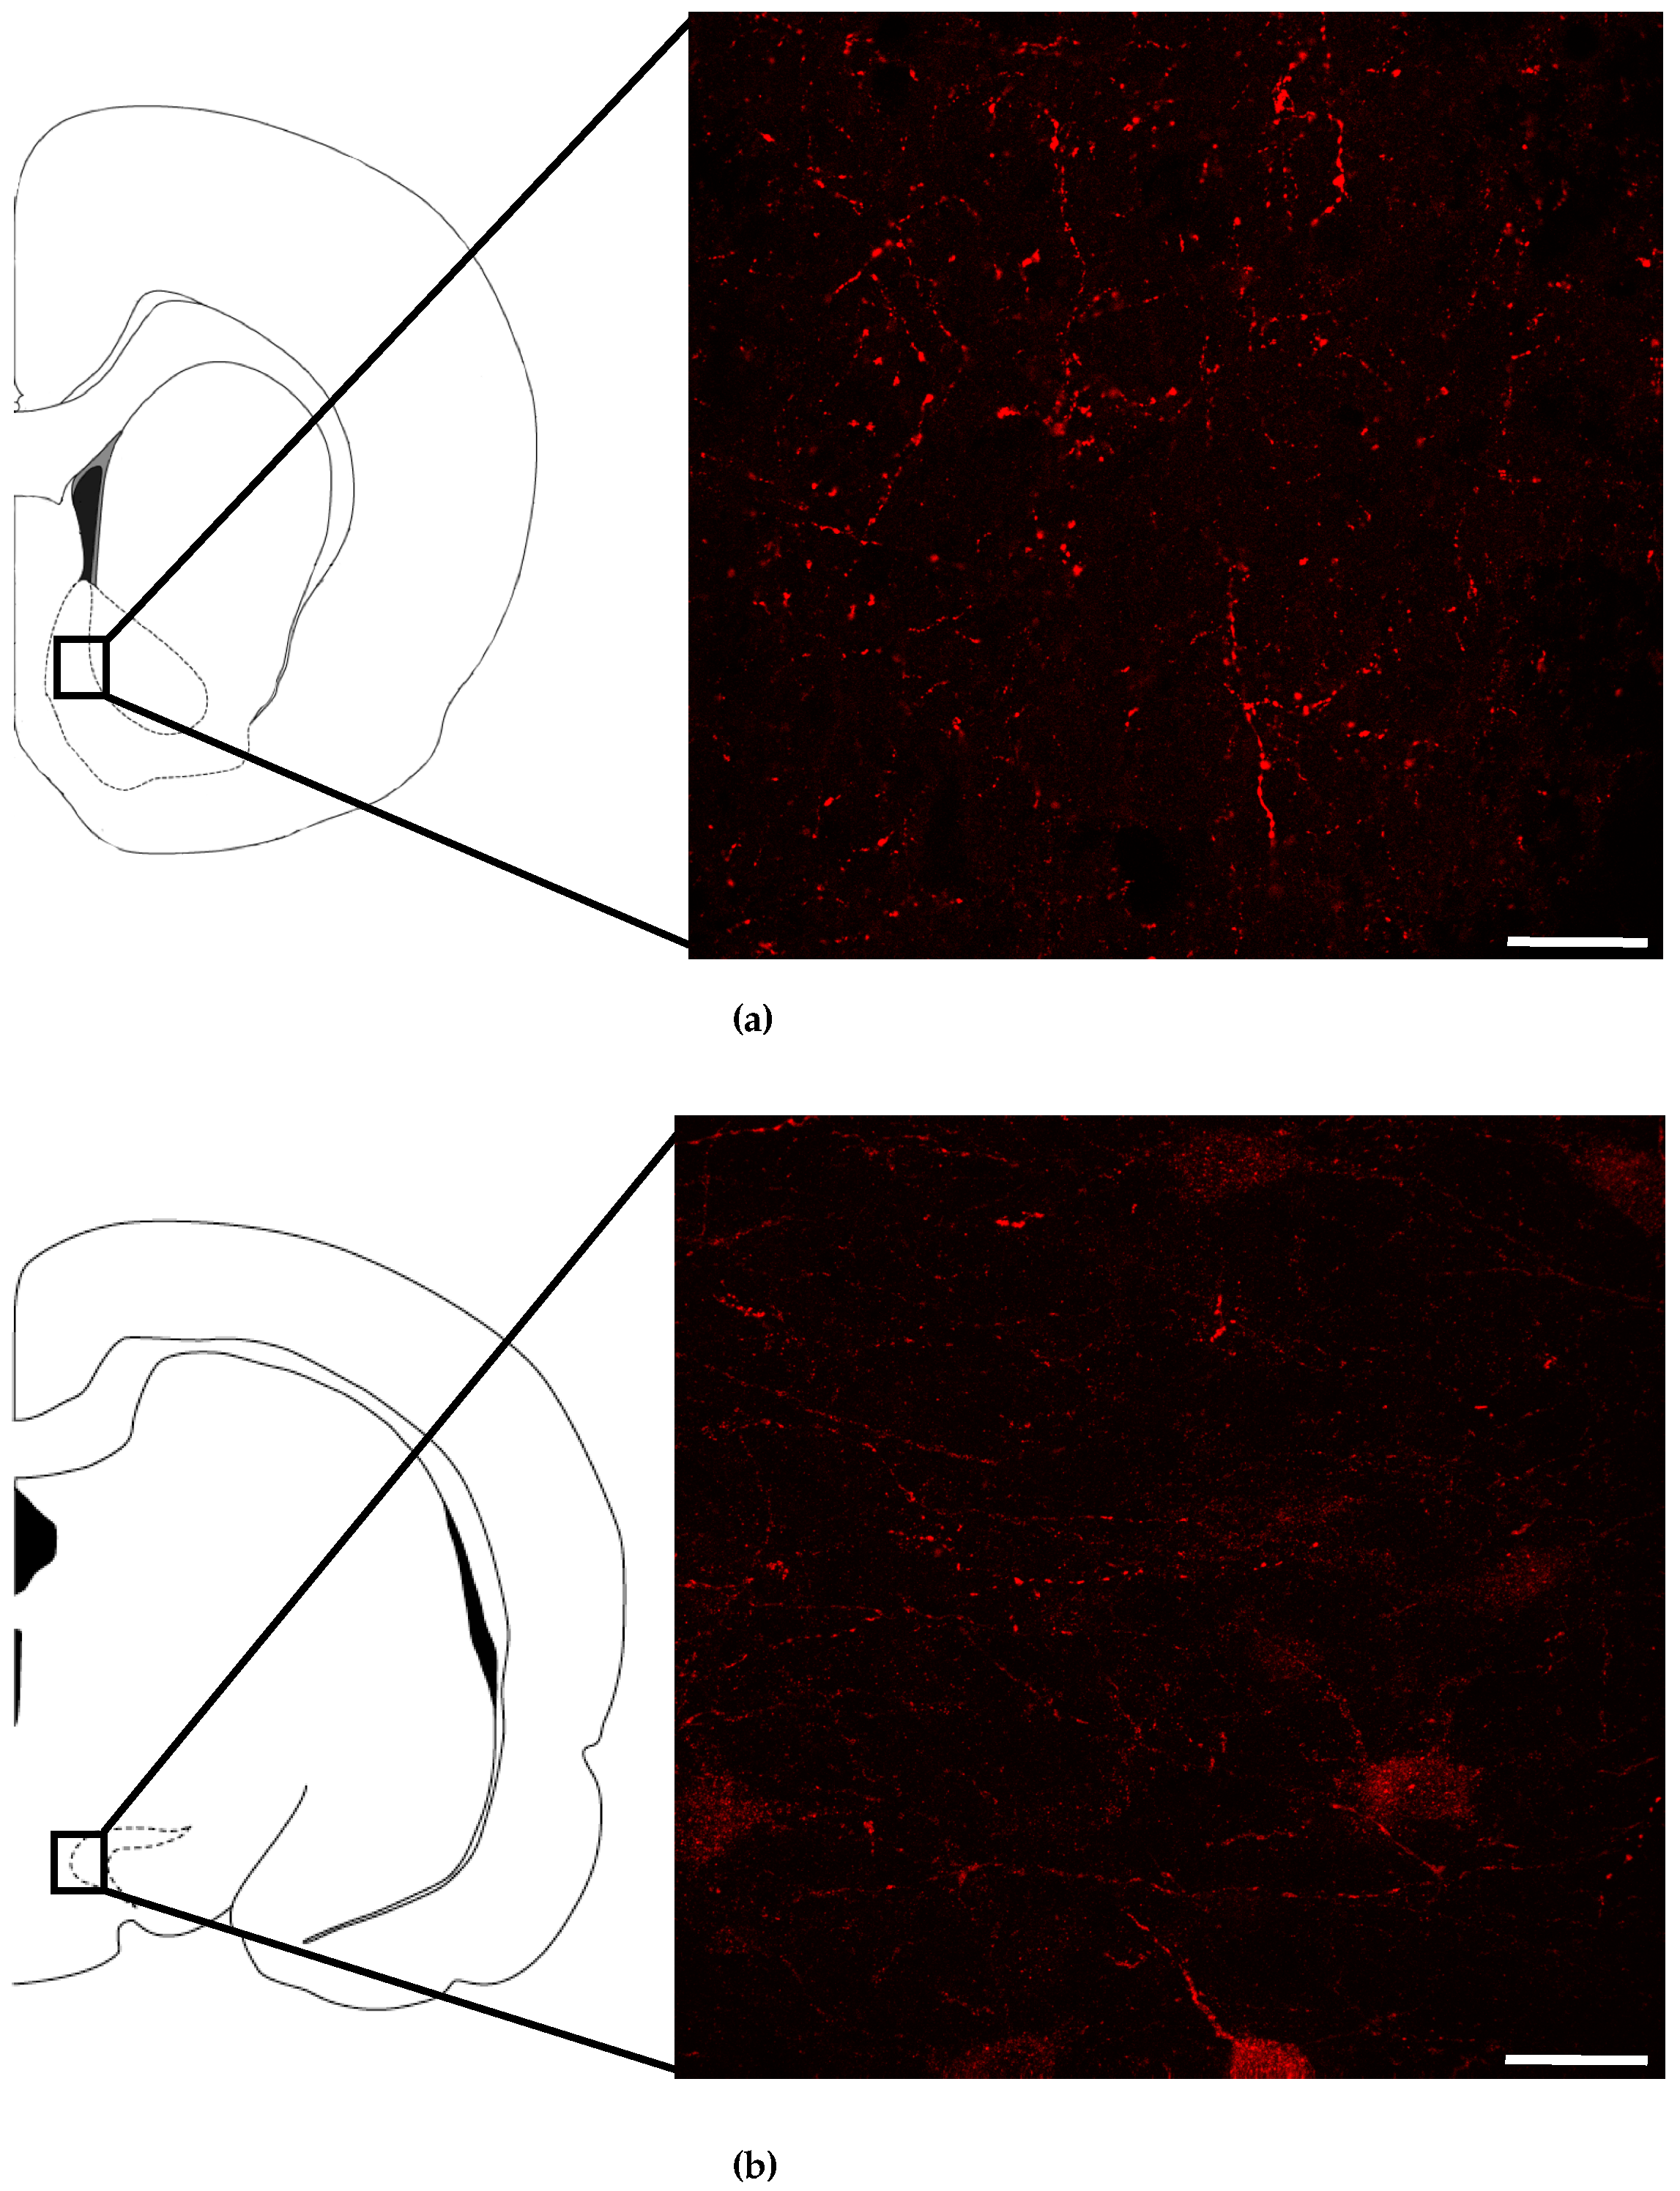

3.1. NMUR2 is Expressed Presynaptically in the NAc and the VTA